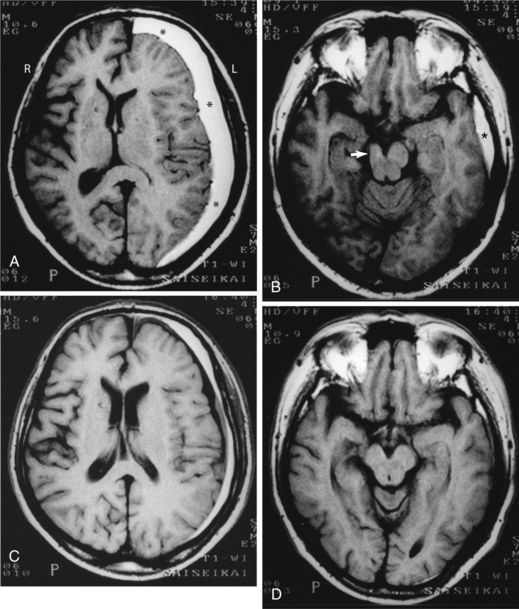

Cerebrovascular disease, the primary cause of stroke, is caused by one of several pathologic processes involving the blood vessels of the brain. The damage may be intrinsic to the vessel, or the stroke may originate remotely, such as when an embolus from the heart or extracranial circulation lodges in an intracranial vessel. The stroke may result from the rupture of a vessel in the subarachnoid space or intracerebral tissue. Fig. 32-1 shows the effects of different types of stroke on brain tissue.98

Figure 32-1 Radiographic images of the brain after stroke. A, An acute infarct with mass effect and compression of the ventricle. B, An acute intracerebral hemorrhage in the hemisphere. C, Amyloid angiopathy with acute hemorrhage; the edema surrounding the area results in a slight mass effect on the midbrain. (Reprinted from Ramsey R: Neuroradiology, Philadelphia, 1994, WB Saunders.)